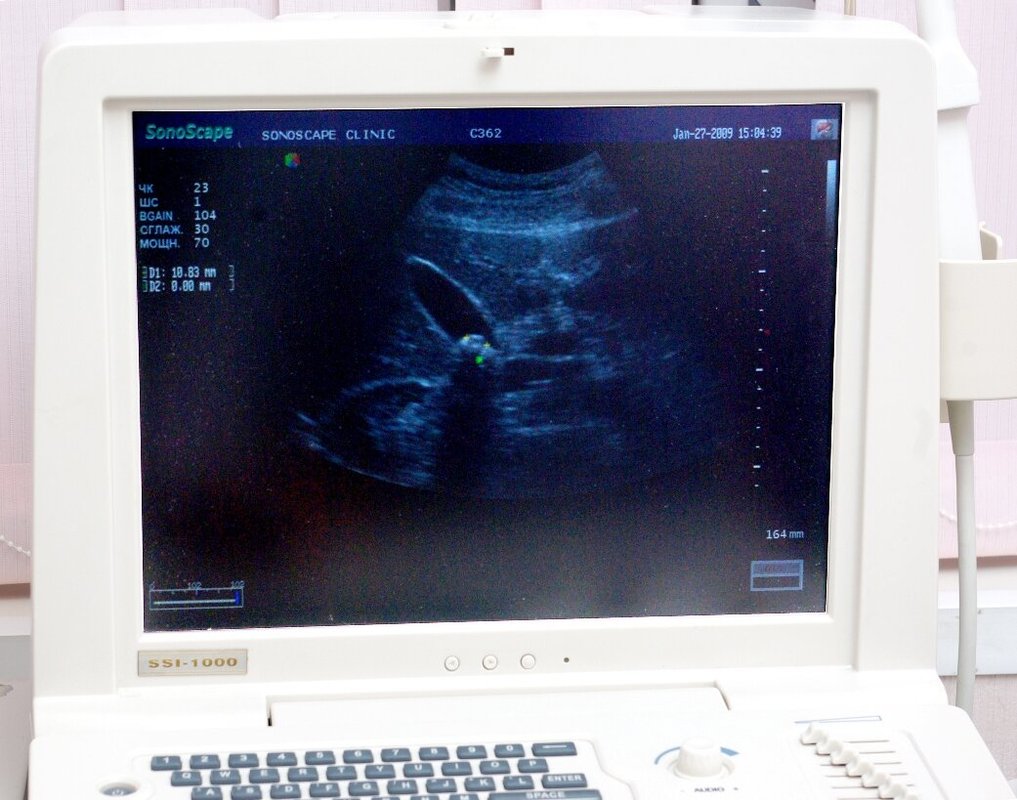

В своей работе мы применяем. В клинике занимаются проведением комплексной диагностики организма на соответствующих аппаратах. У нас вы можете пройти компьютерную томографию, медосмотр, УЗИ, рентгенологическое исследование, МРТ, лабораторную диагностику, функциональное обследование.